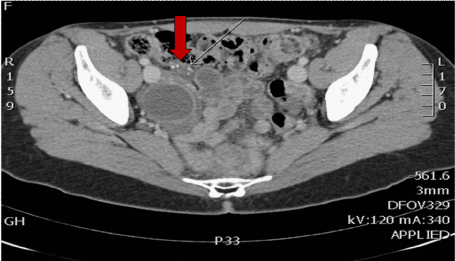

Figure 2: Histology of the appendix tip showed mucinous material within the bowel wall and stroma suggesting a mucocele or mucinous tumour of the appendix. The patient was referred to lower gastrointestinal surgeons. A CT scan found it difficult to visualise the appendix but adjacent to the caecum a 10mm low attenuation lesion with mural calcification was noted suggestive of an appendicular mucocele. No pelvic or retroperitoneal lymphadenopathy was noted and no lesions were noted within the chest.